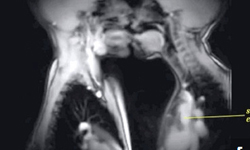

性愛這檔子事,大家就算沒看過也聽說過,或是上過健康教育課(老師都隨便帶過),大概都知道是個什麼樣子,不過!「這樣」的性交過程,想必你絕對沒看過,那就是以「核磁共振(MRI)」的角度,去觀看人類在接吻、心跳加速、懷孕的時候,由「內」而看會是什麼狀況。

接吻時(而且是法式熱吻),心臟加速的模樣

有別於X-Rays和電腦斷層掃描,核磁共振較無輻射問題,因此可以進而發展人體解剖,與內臟方面的研究,我們也才得以看到這麼特別視角的性交畫面,我想,應該沒有比這個更「赤裸」的性愛了吧!